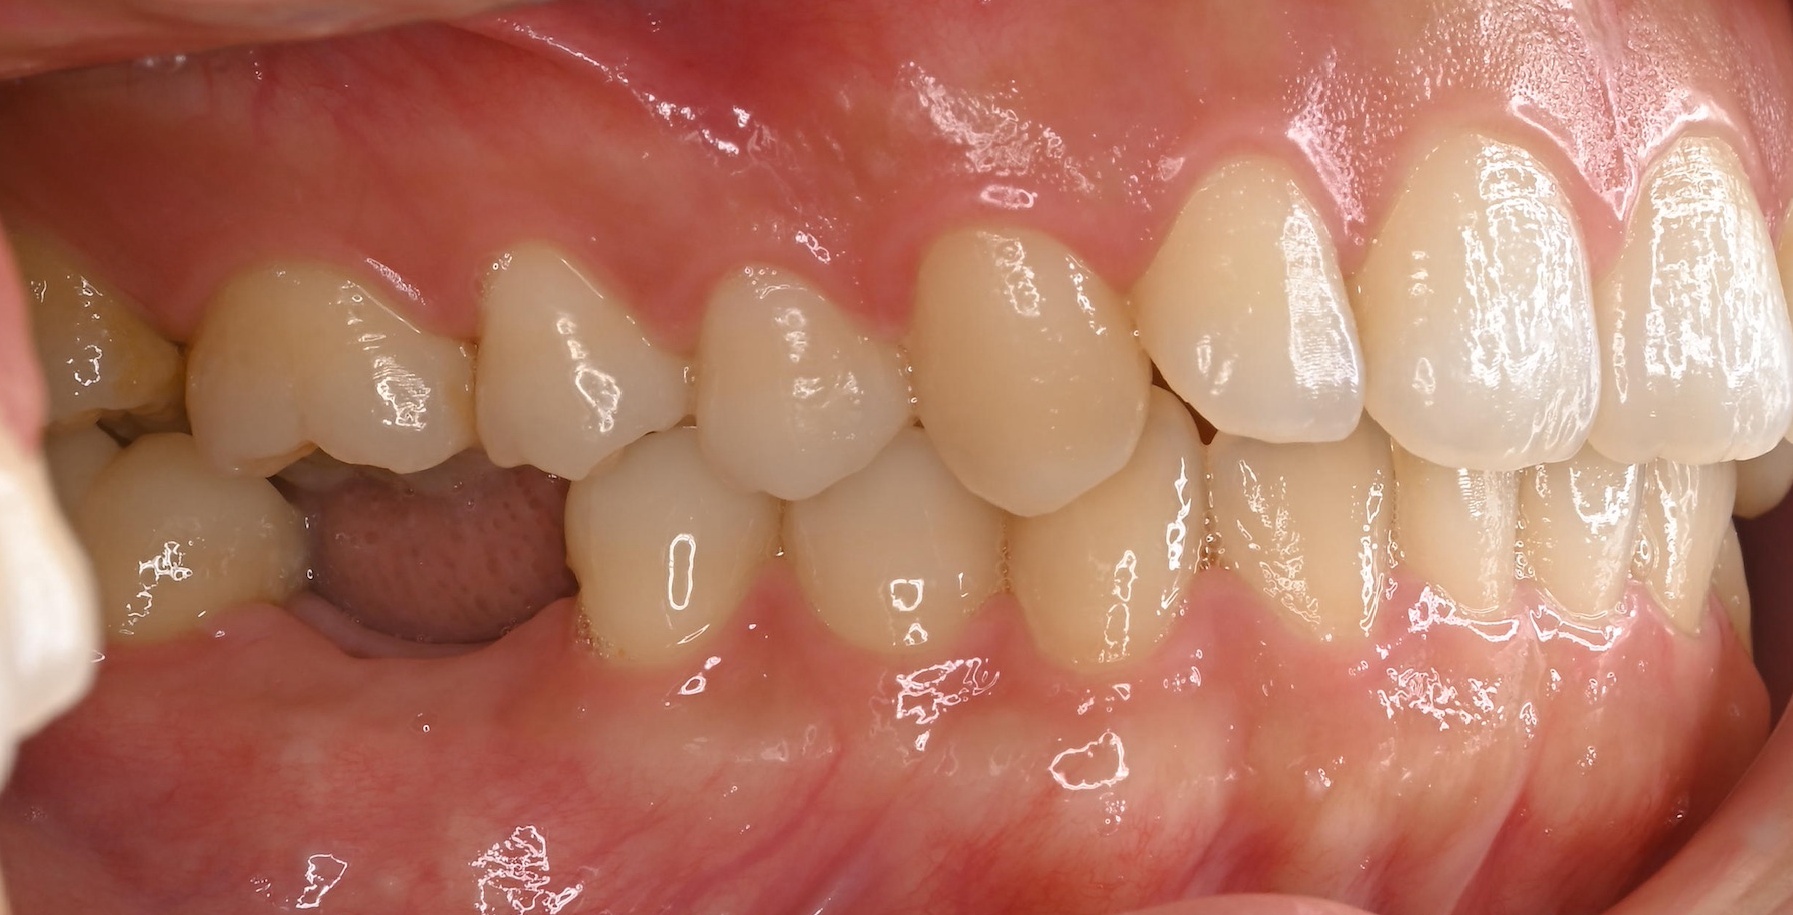

ジルコニアブリッジの症例

Before

After

• After

治療内容

左上1番を他院にて抜歯し、仮歯をボンドで固定された状態で来院されました。

歯を失ったところをブリッジで治す計画をたて、審美的な補綴を目指すためにホワイトニングから行いました。

最終的にジルコニアのブリッジを接着しました。

担当歯科医師:平沼 佳朗

治療期間・回数

約4回

費用

¥462,000

リスク・副作用

ごく稀にジルコニアの先端が割れることがあります。